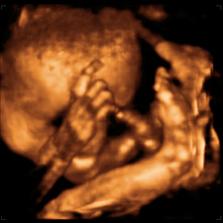

26 tt../1.4.2009/ naša paulínka je stráášne zlatá, boli sme si pozrieť na 4D utz. ..tvárila sa veľmi dôležito, až nafúkano...hehe..vôbec sa nechcela usmievať... nakoniec sa nám aj zasmiala...v brušku veľmi vyvádza, maminke dosť vytláča všetky časti telíčka, čo je niekedy aj dosť bolestivé...ale vydržíme, drobečkovi je tam určite tiež pritesno..a ešte aj stále viac a viac bude... strááášne sa na ňu tešíme🙂))